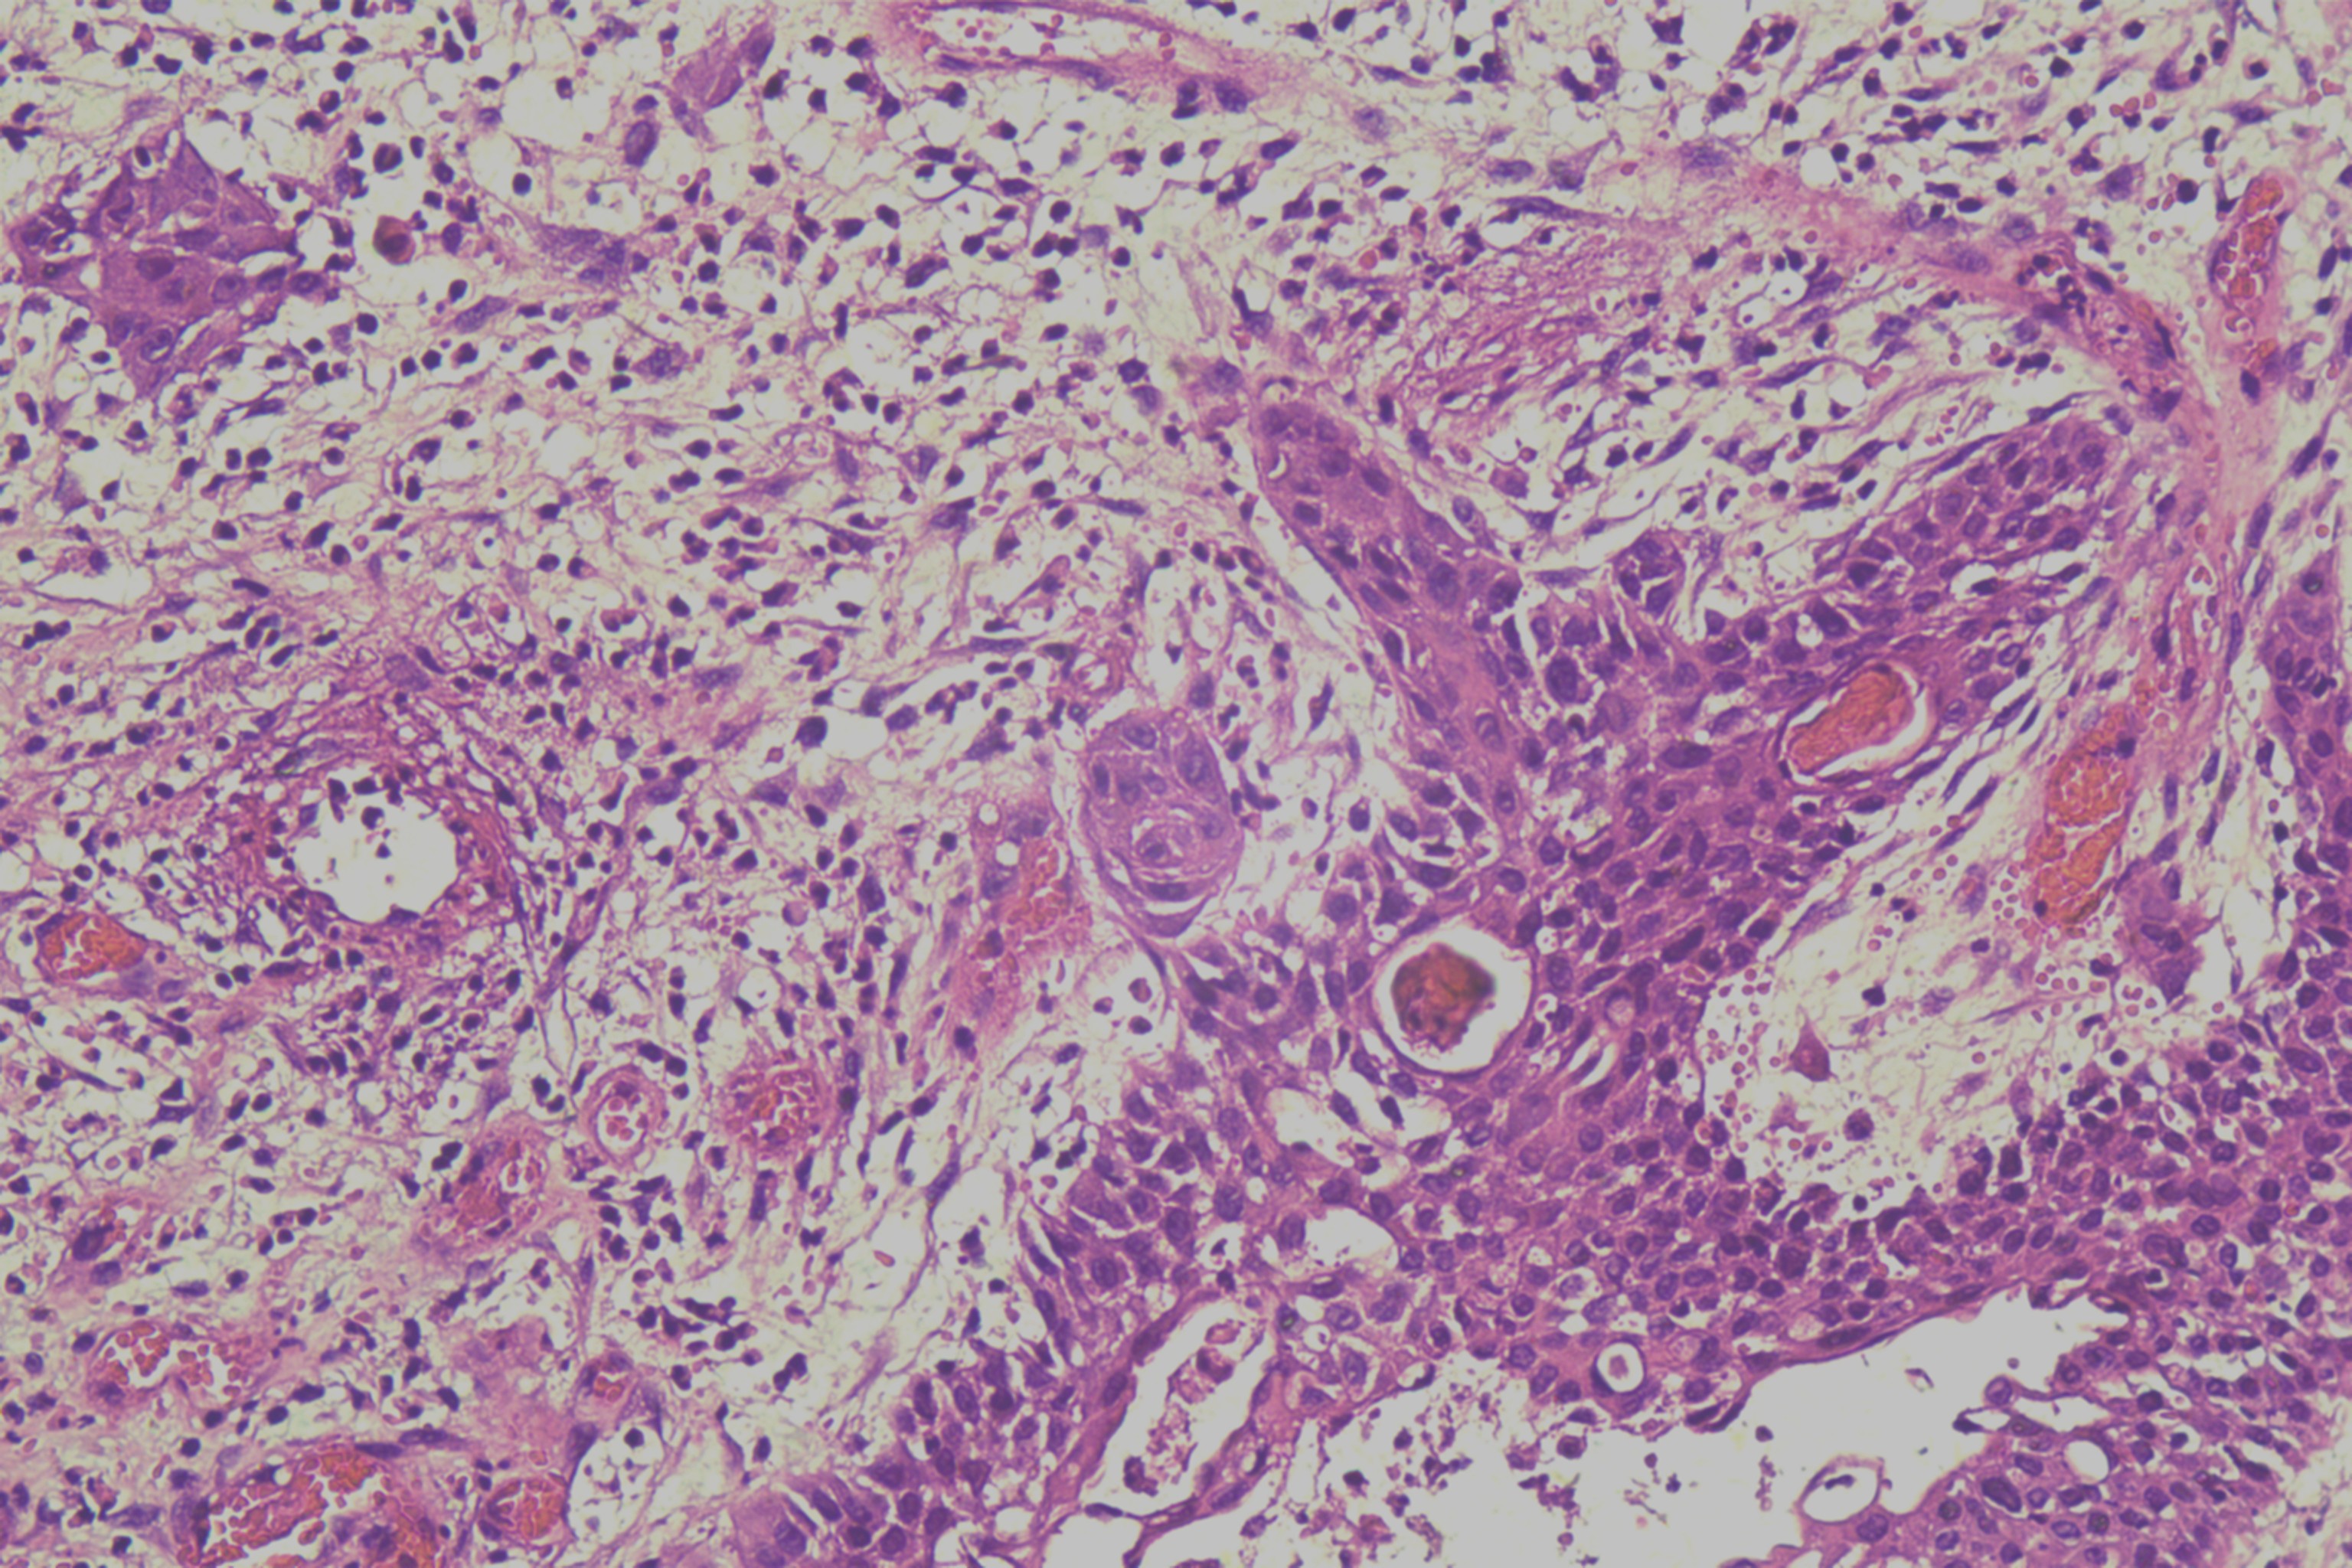

鳞癌?

性别

男

年龄

68岁

头皮肿物20年,包块逐渐增大,反复破溃

头皮肿物(局部活检)

1.5*1*0.3cm灰红碎组织一堆

考虑:基底细胞癌